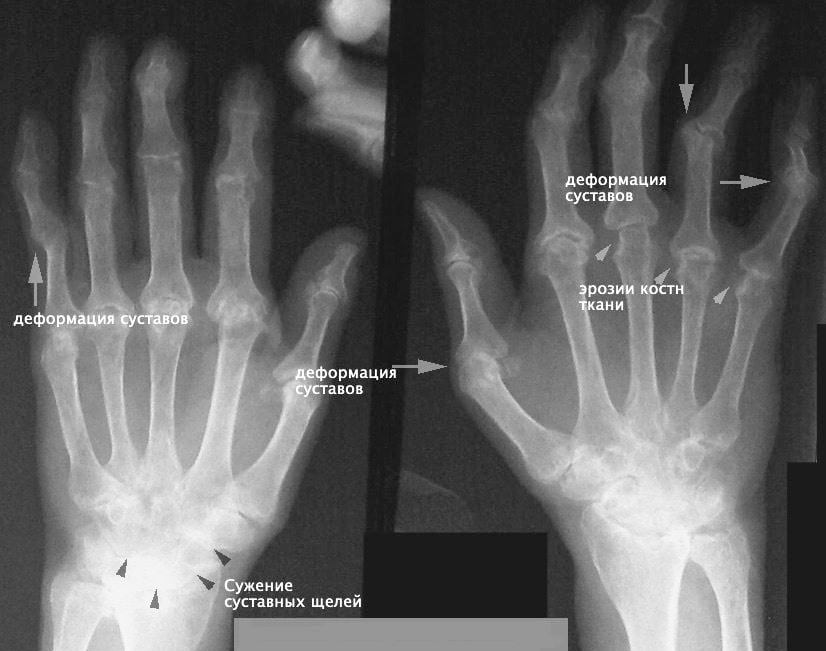

• Рентгенография. Стандартное исследование выполняется в двух проекциях. При необходимости назначают прицельные снимки, рентген симметричных суставов. Методика позволяет визуализировать переломы, вывихи, участки деструкции и остеолиза, изменения суставной щели, разрастания костей.

Рентген рук.